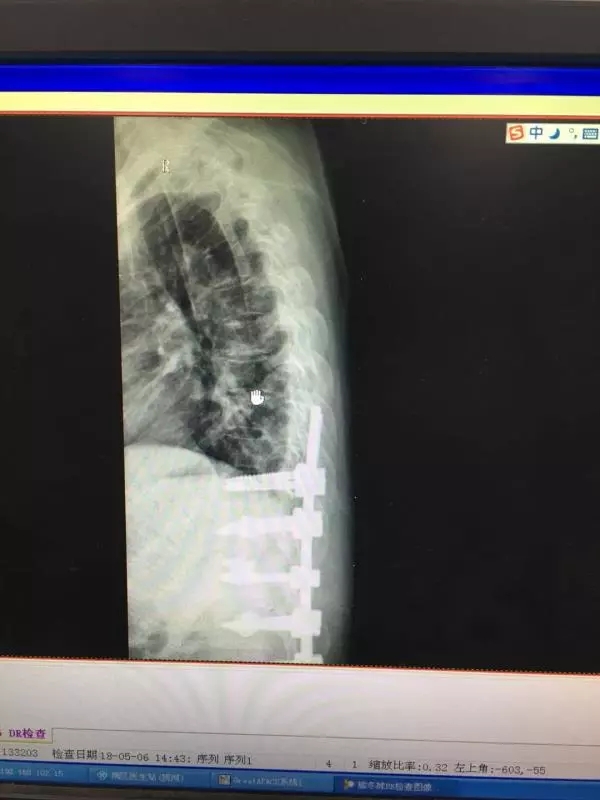

经皮椎弓根螺钉同样也是通过经皮做一小切口,利用C臂机作为医生的眼睛,依次进入导针,扩孔,后期进入椎弓根螺钉。操作稍有不慎,螺钉就可能进入椎管内,造成截瘫。如下图所示: